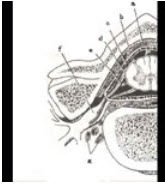

23、问答题

如图所示a、b分别为脊髓的哪个部位,试述两部位的损害主要区别点是什么?

141、配伍题

如图a所示为脊髓和神经根()

如图b所示为脊髓和神经根()

如图c所示为脊髓和神经根()

如图d所示为脊髓和神经根()

如图e所示为脊髓和神经根()